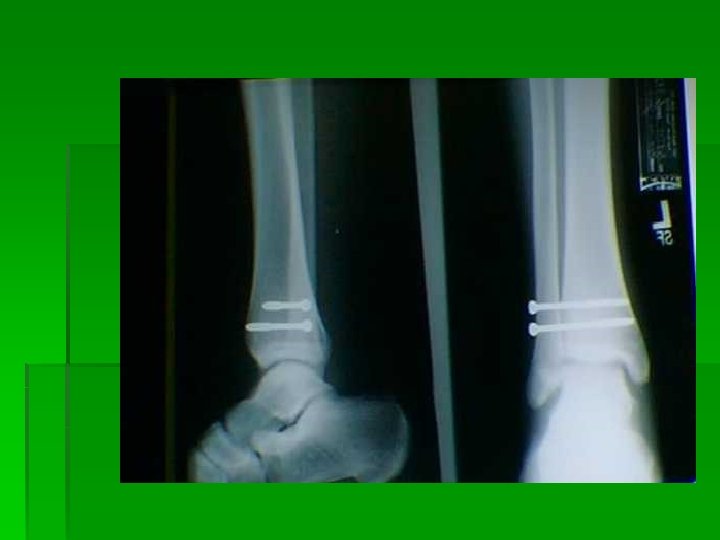

Distal Fibula fracture with associated medial deltoid ligament disruption. This injury is frequently the result of the foot being planted with a valgus load applied to the leg.

Notice the disruption of the medial deltoid ligament and the widening between the medial malleolus and the talus. This is indicative of a ruptured deltoid ligament.